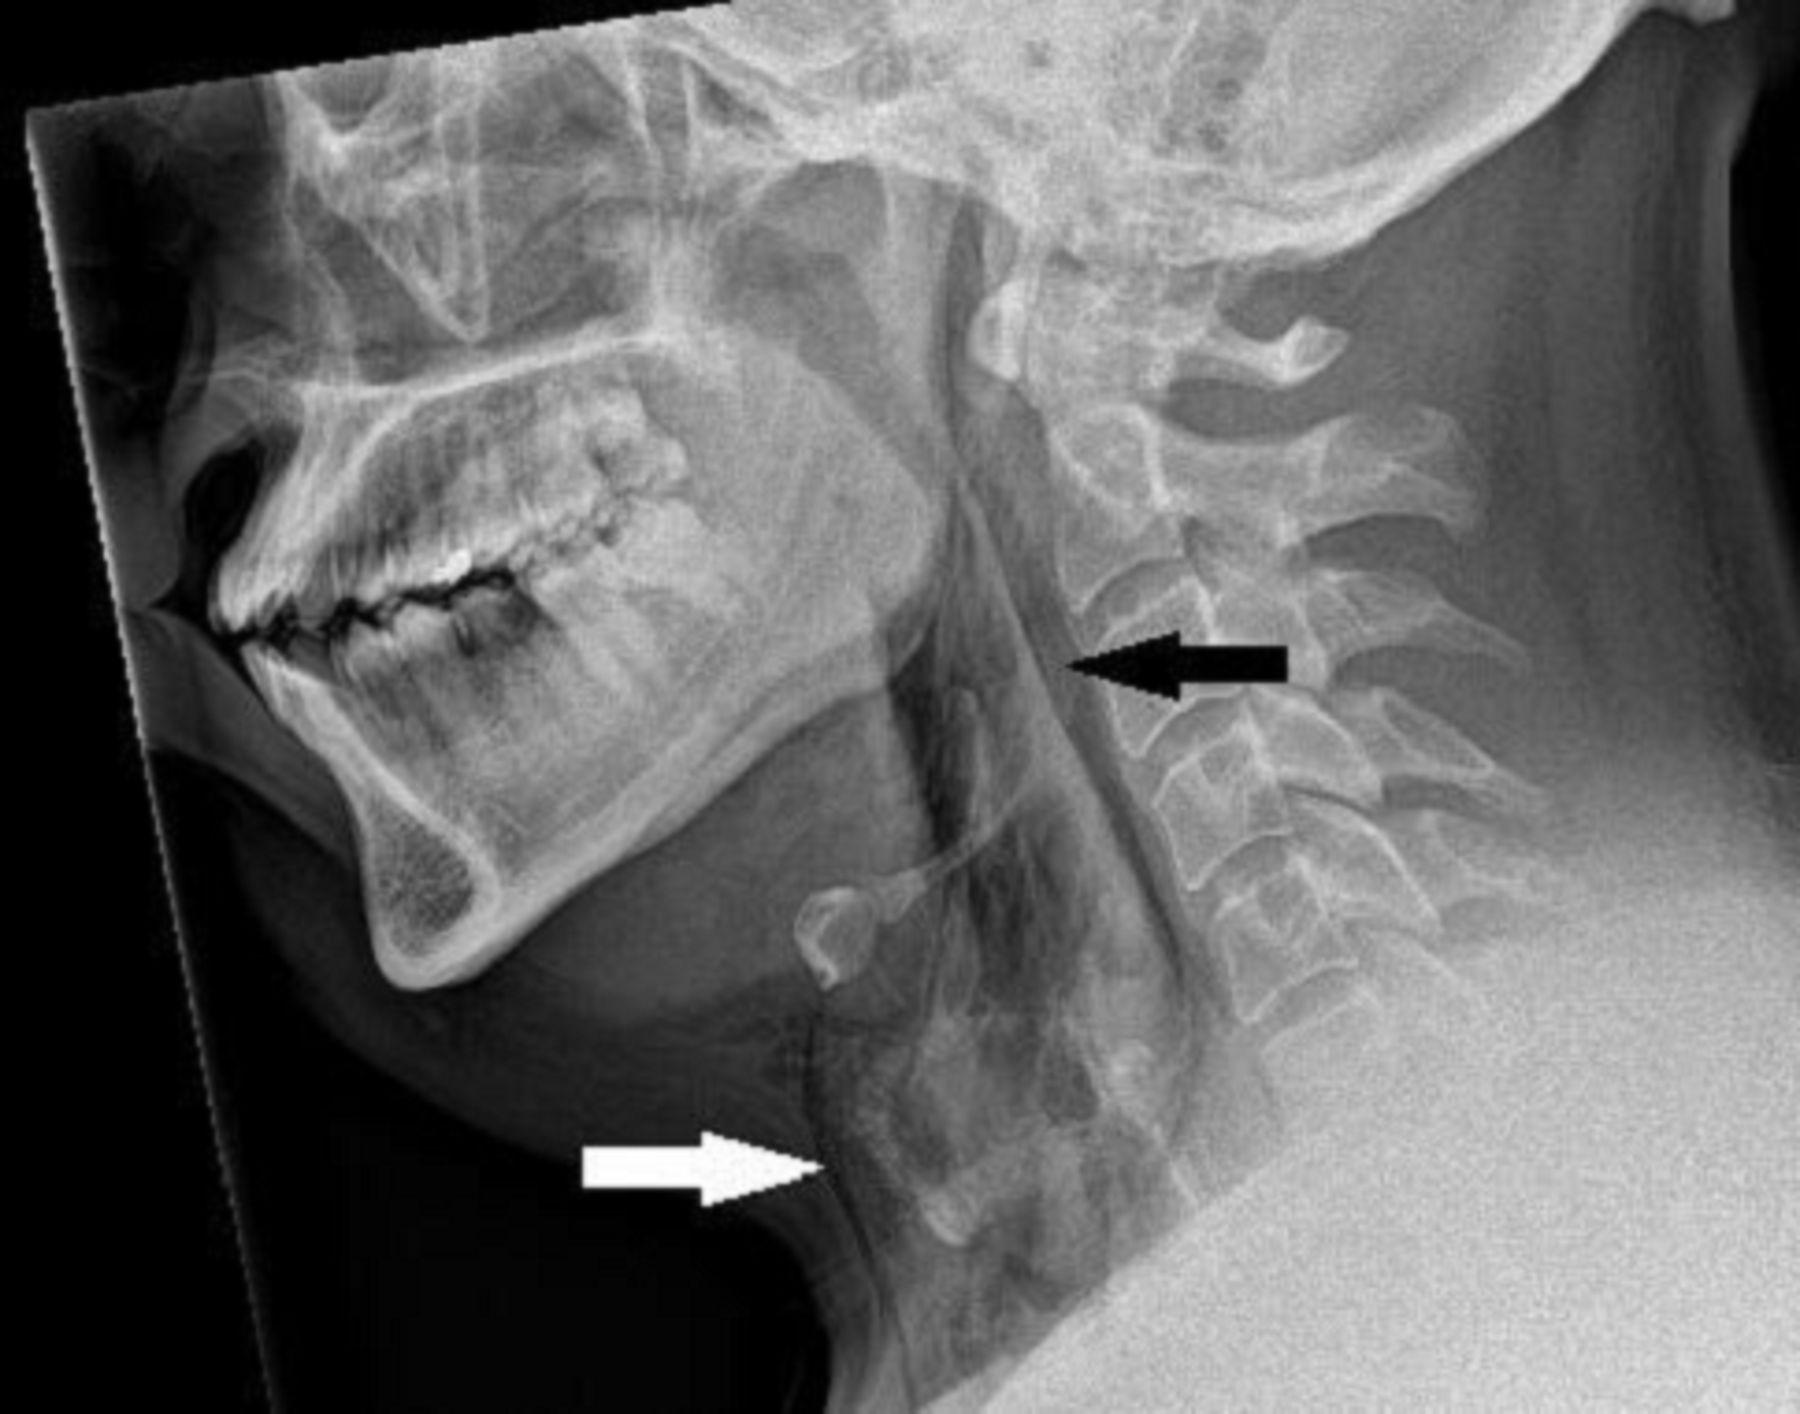

經過X光檢查及電腦掃描後發現,男子的第三和第四節頸椎之間有一處2毫米乘2毫米乘5毫米的氣管撕裂,還有縱膈腔氣腫和頸部手術性肺氣腫,所幸不危及生命,亦不用做手術。男子接受止痛藥和花粉症藥物治療,留院觀察48小時後出院,醫生提醒他兩周內不要有任何劇烈運動。他5周後再接受檢查,顯示氣管撕裂已完全癒合。